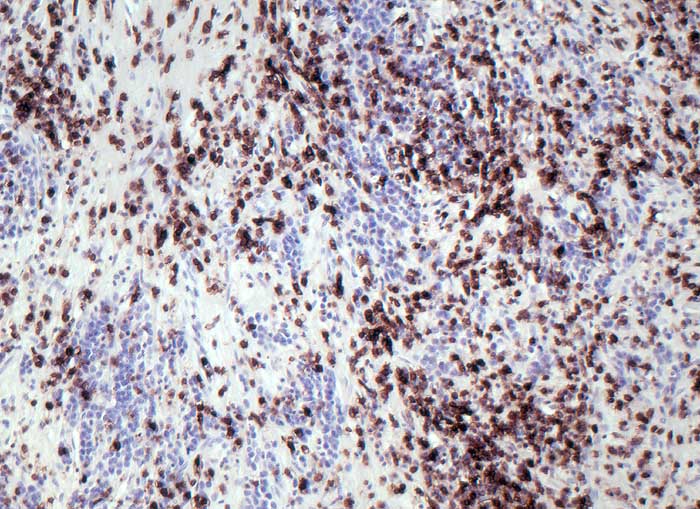

Lymphoepitheliom-artiges Magenkarzinom (medulläres Karzinom)

Die grösseren Tumorzellen reagieren nicht mit dem panleukozytären Marker CD45.

Magenstumpfkarzinom 20 Jahre nach Billroth II-Resektion wegen Ulcus duodeni.

Die Prognose bei fortgeschrittenen Tumoren ist wesentlich besser beim medullären Karzinom als bei konventionellen Adenokarzinomsubtypen des Magens.

Histologie

Immunhistochemie

CD45 (LCA)

320